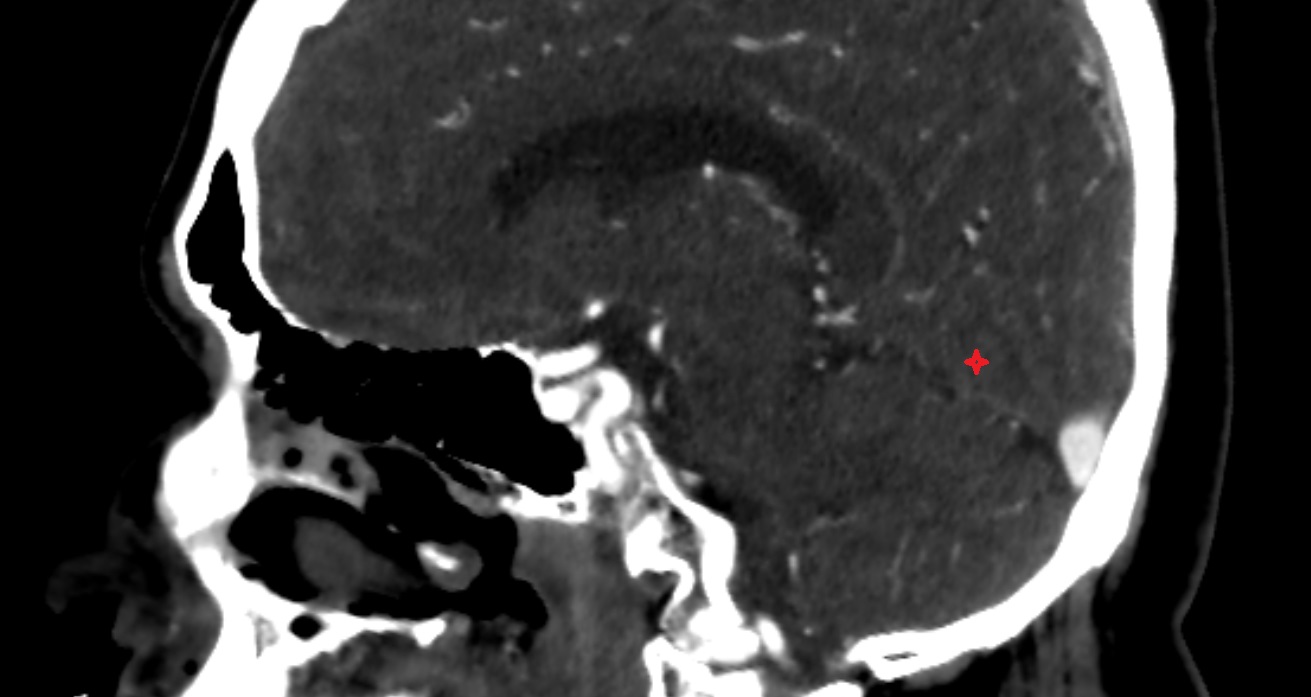

- Cerebellum